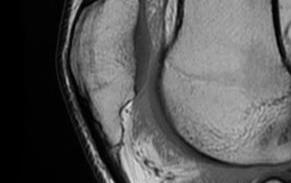

MRI

Cyst / Degeneration

Traction spurs / calcification / ossicles